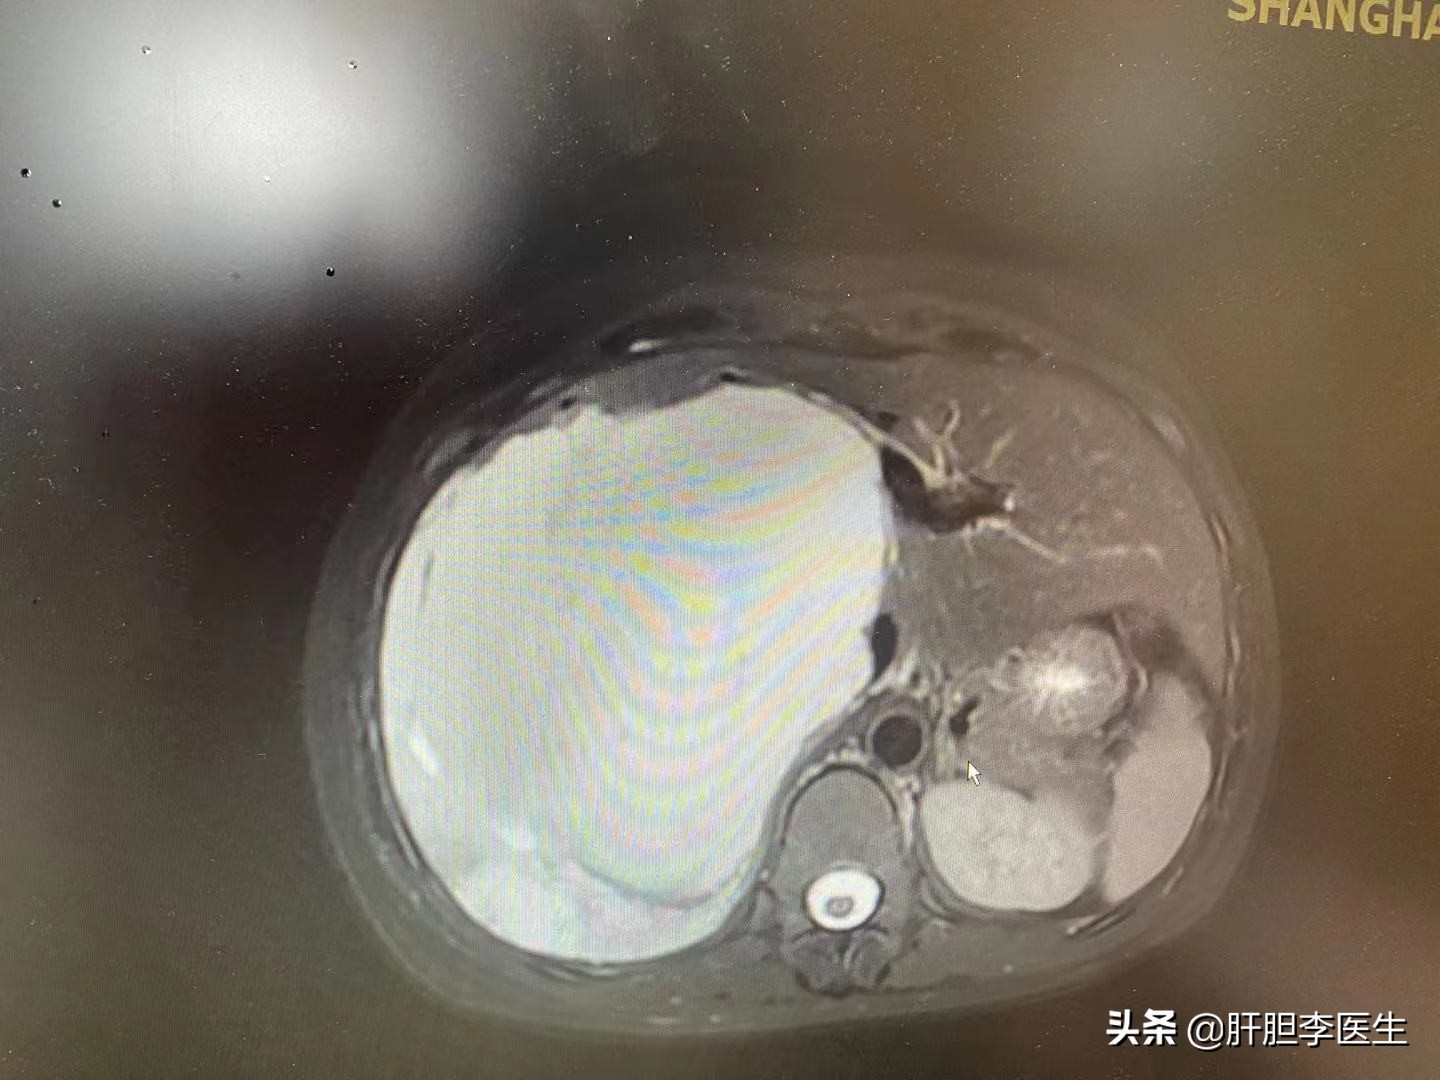

这次来复查的时候,直接做了肝脏的增强核磁,虽然知道血管瘤会增大,但是没想到看到片子的时候还是有点出乎意料,血管瘤的最大直径已经达到了17cm,几乎右边的肝脏都是血管瘤了,只剩下左边半个肝脏在维持正常工作了。当然手术的风险并不止这一点,而是血管瘤紧紧地贴在下腔静脉上,手术切除血管瘤就要把血管瘤从下腔静脉上一点一点地扒下来,在这个过程中随时有可能出现大出血的情况,而且下腔静脉的出血非常凶险,可能会有生命危险。